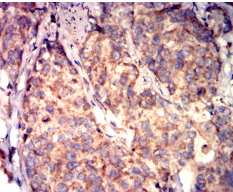

IHC    1/200-1/1000